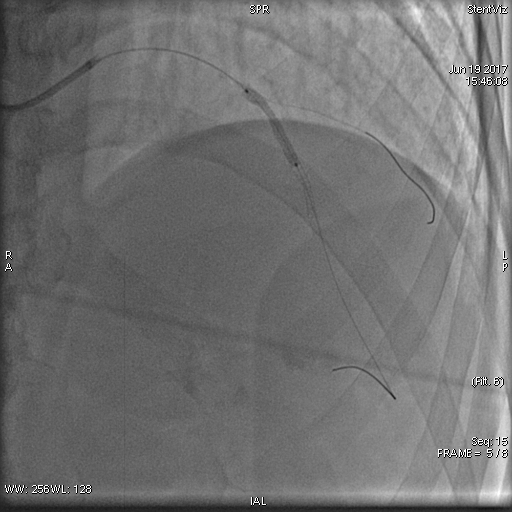

治疗方案及结果: 前降支中远段重度弥漫性狭窄,行支架植入术治疗,术后罪犯血管开通,血流通畅,达TIMI3级。 病例点评及临床价值: 前降支近段支架释放后,发现支架球囊未完全扩张,后扩后情况未明显改善,应用StentViz示:前降支近段支架与远段支架重叠良好,近段支架近端未完全扩张,有“小腰”,呈“狗骨头效应”,同时血管局部钙化斑块明显。明确情况后,继续加压扩张后,支架完全扩张,血流通畅达TIMI3级。 在本病例中,术中StentViz即刻评价了支架释放效果,精准的显示了两支架扩张、重叠和贴壁的情况,把“几乎看不见的支架”精准的呈现了支架的每一个细节,同时也显示了透视和采集不易发现的钙化病变,提高了诊断的精准度,明确了进一步的治疗方案。